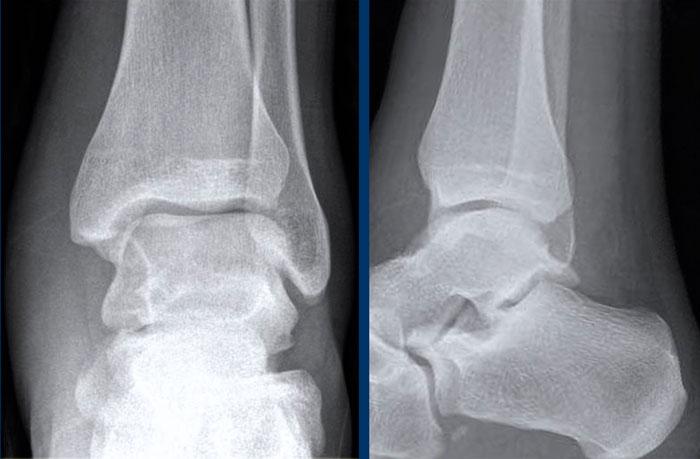

Ca 1 – Chấn thương cổ chân

Hình ảnh cho thấy những dấu hiệu gì và có ý nghĩa như thế nào?

Nhấp vào hình ảnh để xem phóng to.